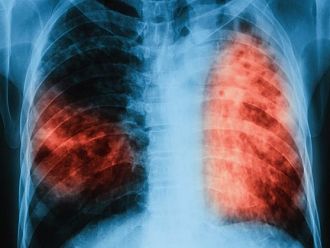

В периода 12-16 март 2018 г. ще се провеждат безплатни прегледи за туберкулоза в лечебни заведения за диагностика и лечение на туберкулоза във всички областни градове на страната. Поводът е предстоящият Световен ден за борба с туберкулозата – 24 март, който тази година ще премине под надслов „Търсят се: Лидери за свят без туберкулоза“.

През последните години в страната ни се наблюдава тенденция за намаляване на заболеваемостта – от 39.1 на 100 000 през 2006 г. до 21.3 на 100 000 през 2016 г. Спадът се дължи на предприетите дейности за превенция и контрол на туберкулозата на национално и регионално ниво, както и на съвместните действия на Министерството на здравеопазването, специализираните лечебни заведения и неправителствените организации, работещи с уязвимите групи.

Туберкулозата е лечимо заболяване, стига да бъде открита навреме и да бъде проведено качествено лечение, съобразено с международните стандарти. В България диагностиката, лечението и профилактиката ѝ са безплатни за всички, които се нуждаят, независимо от техния здравноосигурителен статус.